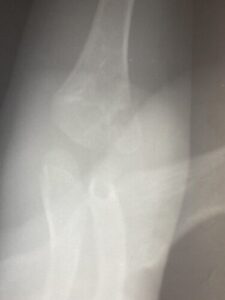

春日部市市民活動センター(肘関節脱臼)

肘関節前方脱臼の1症例について